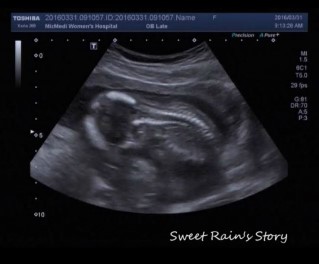

임신 25주 - 임신성당뇨검사, 임신성당뇨재검사, 임당검사

이번주 월요일 남편이랑 함께 임신성 당뇨 검사를 하러 미즈메디 병원에 갔지요. 저의 주치의 쌤은 25주에 ...

임신 25주 - 정기검사, 25주차 증상

울 사랑하는 복덩이가 우리 부부에게 찾아 온지도 벌써 25주가 되었어요. 24주차에는 살짝 피가 비쳐서 응...